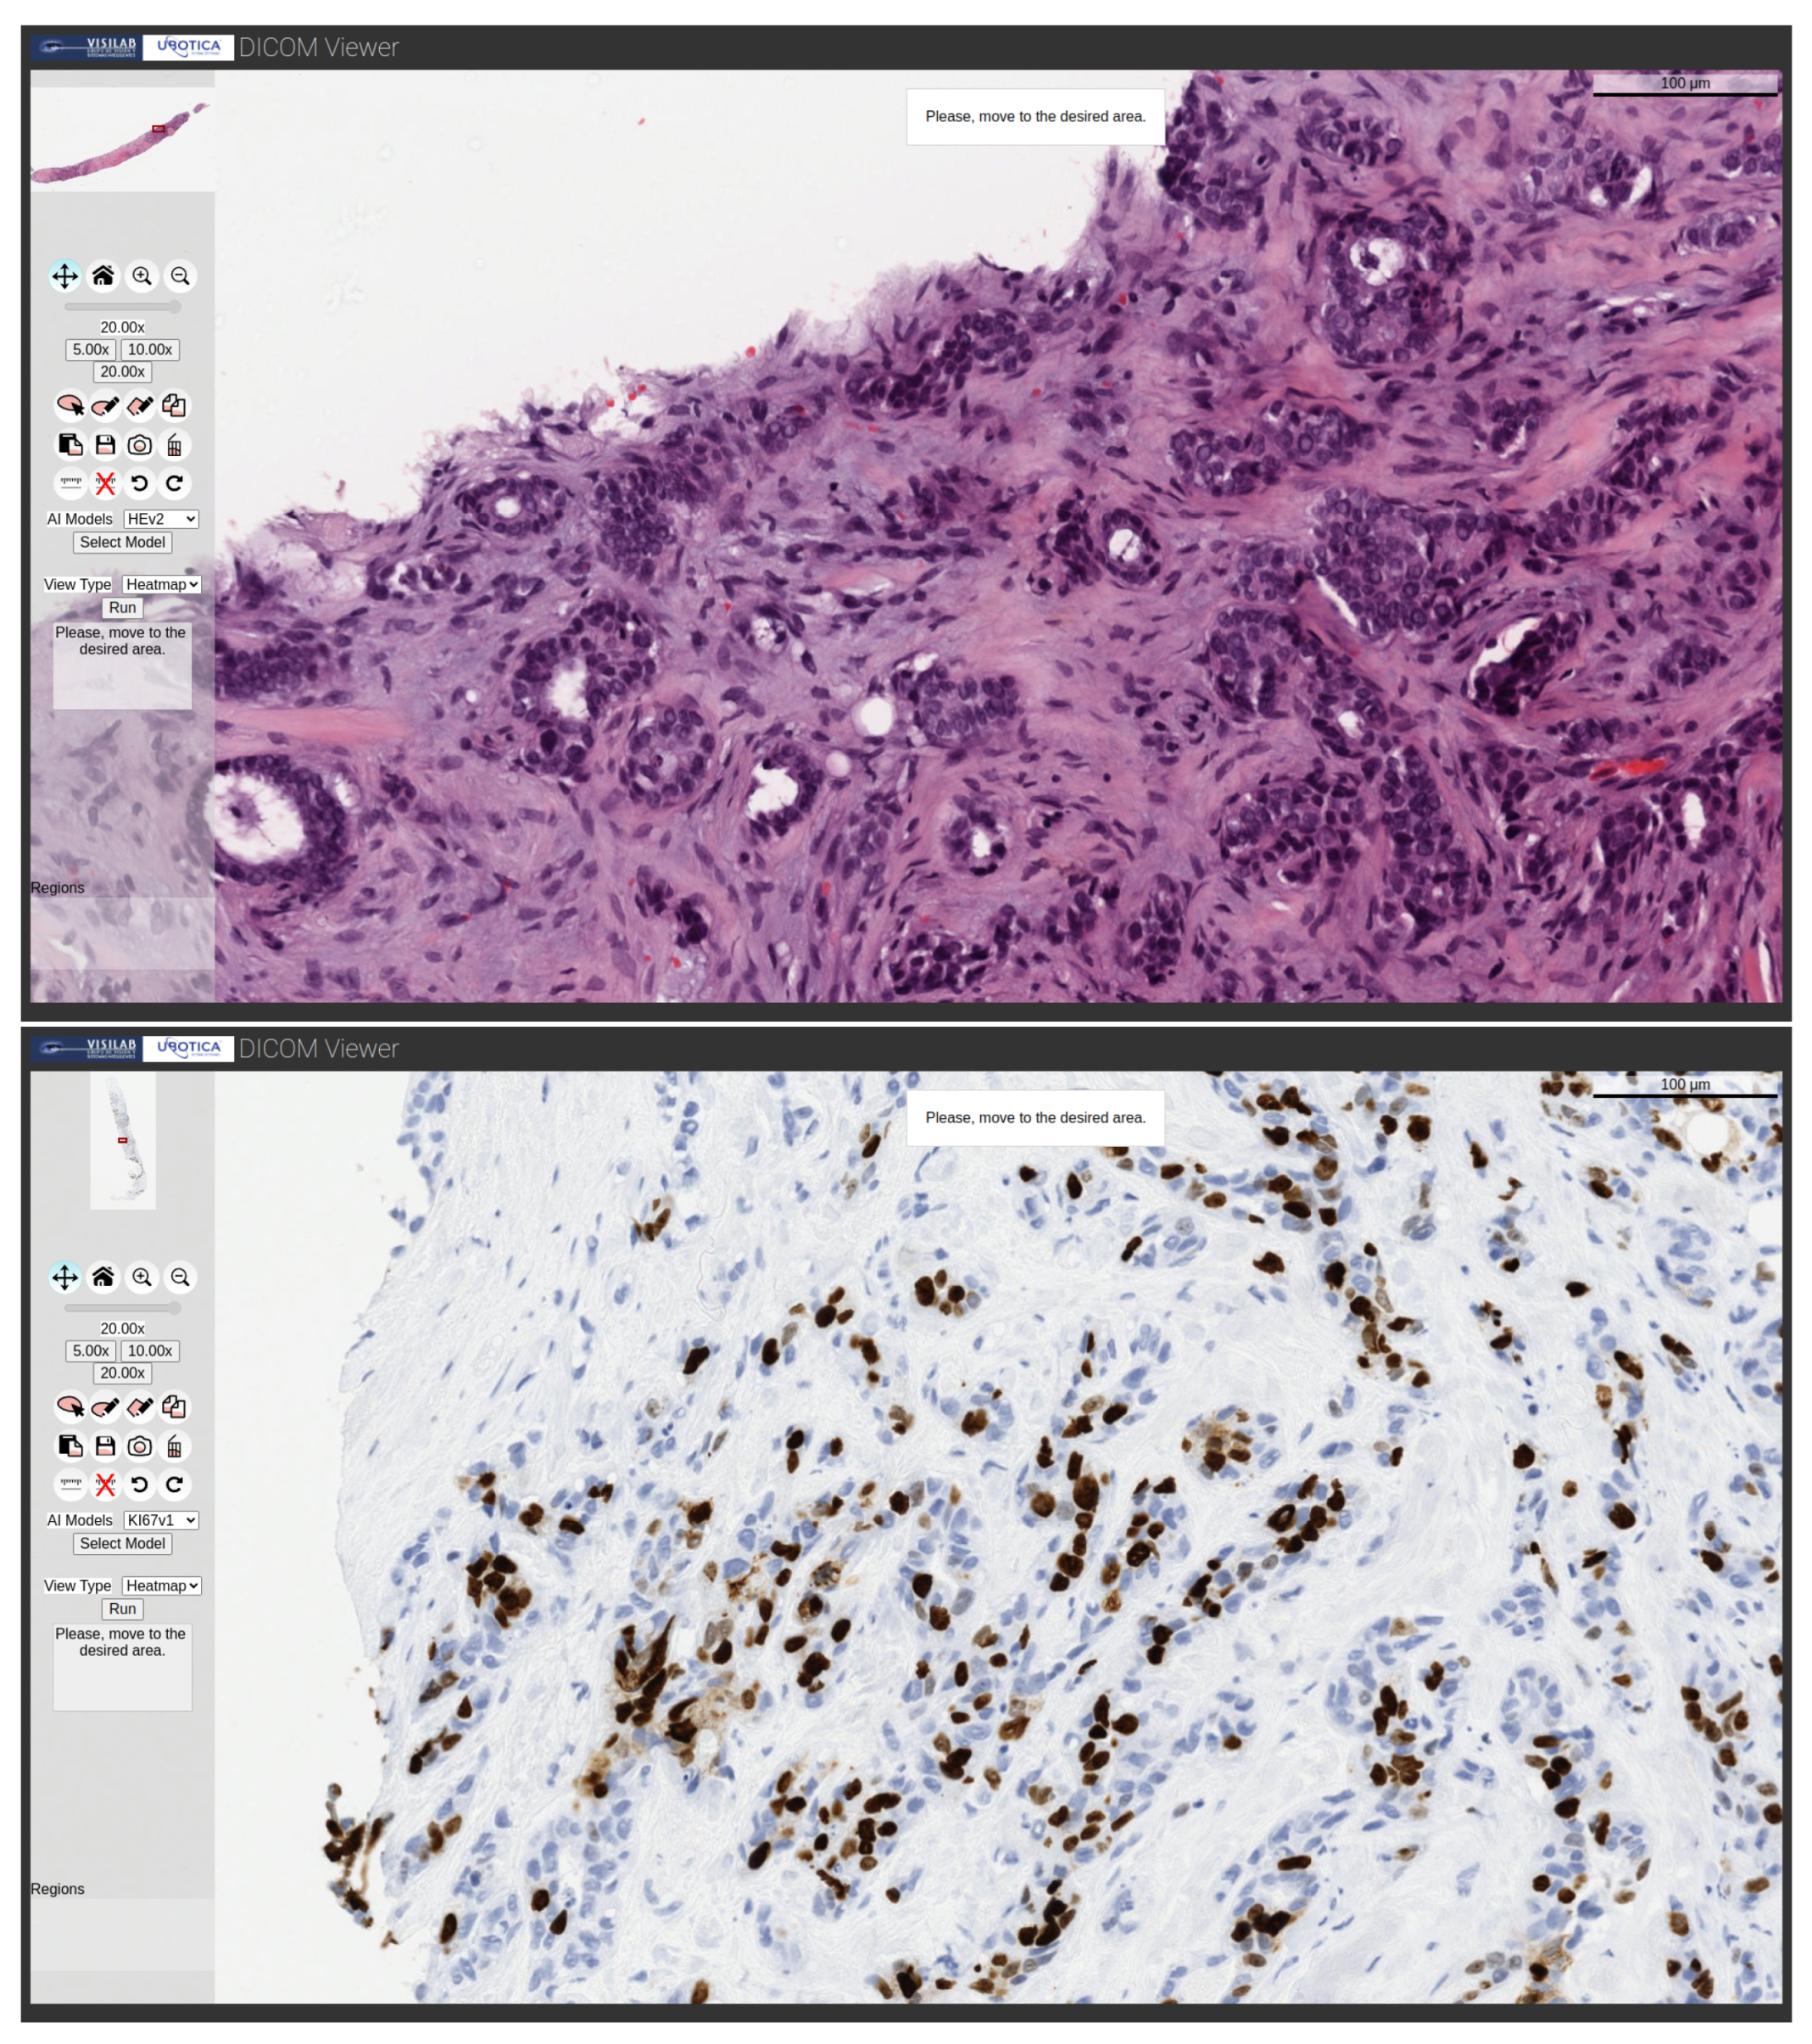

Figure 3 shows the visualization of various WSI samples from various biopsies stained with H&E, Ki67 and HER2, as well as the selection of regions of interest (ROI) on the WSIs using the editing tools of the viewer.

• The user selects the model that he/she wants to run from the available models and the type of result to be obtained or view types, i.e., the possible outputs for displaying the results, which is a heatmap or bounding boxes when appropriate (Figure 4).

• The user clicks on the Run button and the viewer zooms in to the magnification required by the model to make the inference. The default value is 20×, which displays the message “Please move to the desired area” in the text box and in a pop-up window, as shown in Figure 5.

• Heatmap: The classification of each of the analyzed patches is depicted on a heatmap. The processing is localized to the user-marked augmented region, but, in this case, a tiling process is carried out in which each patch has the input size of the neural network. Each of the individually obtained patches is subjected to the inference procedure, resulting in the generation of a map that shows the classification of each patch. This view is offered for the H&E and Ki67 models. Some examples are illustrated in Figure 7.

Figure 7. Examples of H&E and Ki67 model processing showing the outcomes with heatmap type output.